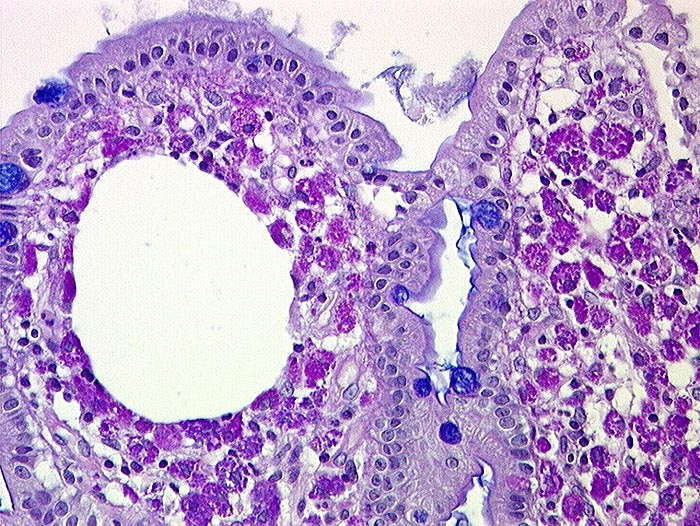

AP/ Morbus Whipple

Morbus Whipple

Dünndarm

Pathologischer Befund